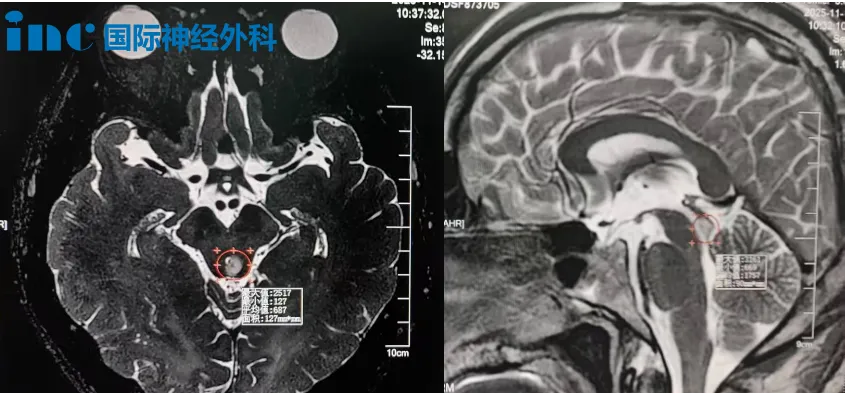

37岁男性患者吴先生,小脑与脑干两处存在肿瘤病灶。在尝试所有保守治疗方案无效后,他最终选择接受手术治疗,通过一次开颅手术同时切除两处病变。

两年前体检发现颅内占位性病变,今年复查磁共振显示:左侧小脑半球存在约1.2×0.9×1.0厘米异常信号,第四脑室轻度受压;中脑背侧左侧份另见约0.5厘米异常信号,中脑导水管轻度受压。持续头昏、记忆力下降、反应迟钝等症状已严重影响其生活质量。

咨询巴教授后获悉,虽然目前肿瘤体积不大,但脑干位置特殊,教授建议尽早进行择期手术。此时手术具有多项优势:病灶较小,手术难度相对可控;可一次性处理两处病变;能有效预防神经功能进一步受损,同时避免未来病灶增大导致手术风险升高。需要强调的是,虽非急诊手术,但拖延可能导致不可逆神经损伤,因此把握时机非常关键。